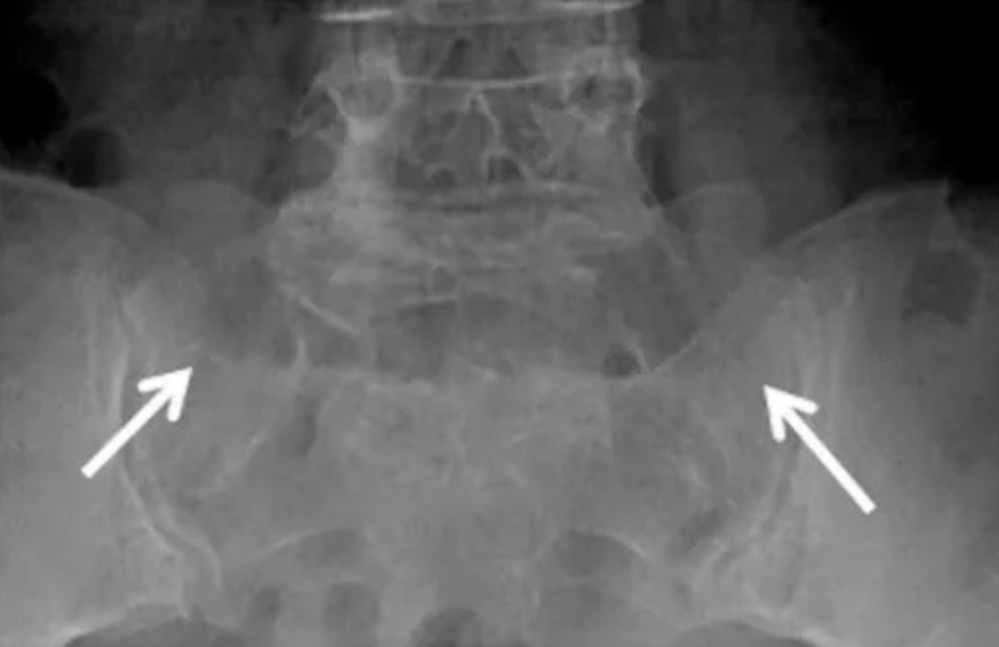

IIb型:双侧横突与骶骨形成假关节伴硬化

(白箭指向假关节,但很难清晰显示)